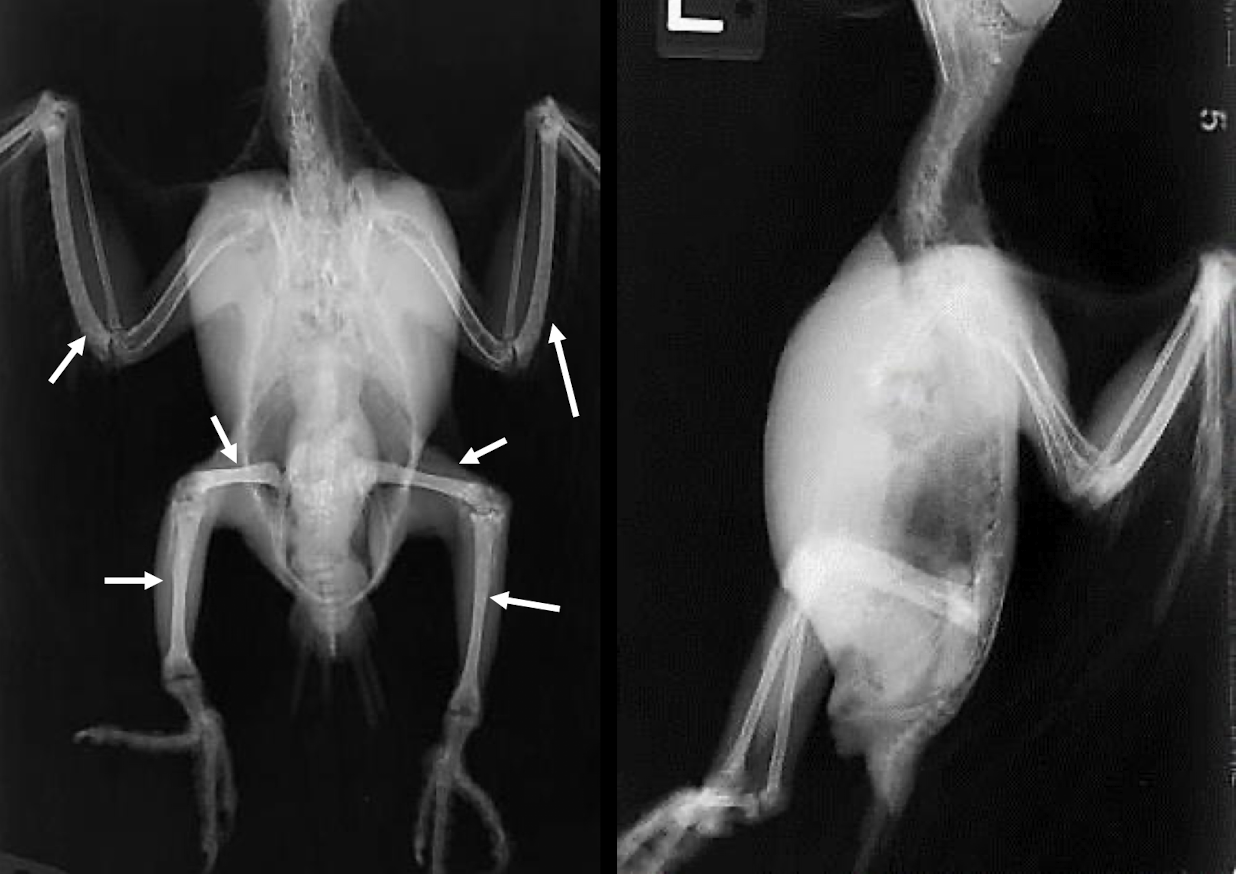

What is wrong here?

obesity

Fungal airsacculitis